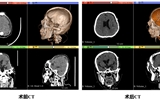

甘肃首例!兰大二院4D PEEK支架修复颅骨,开启动态融合新里程